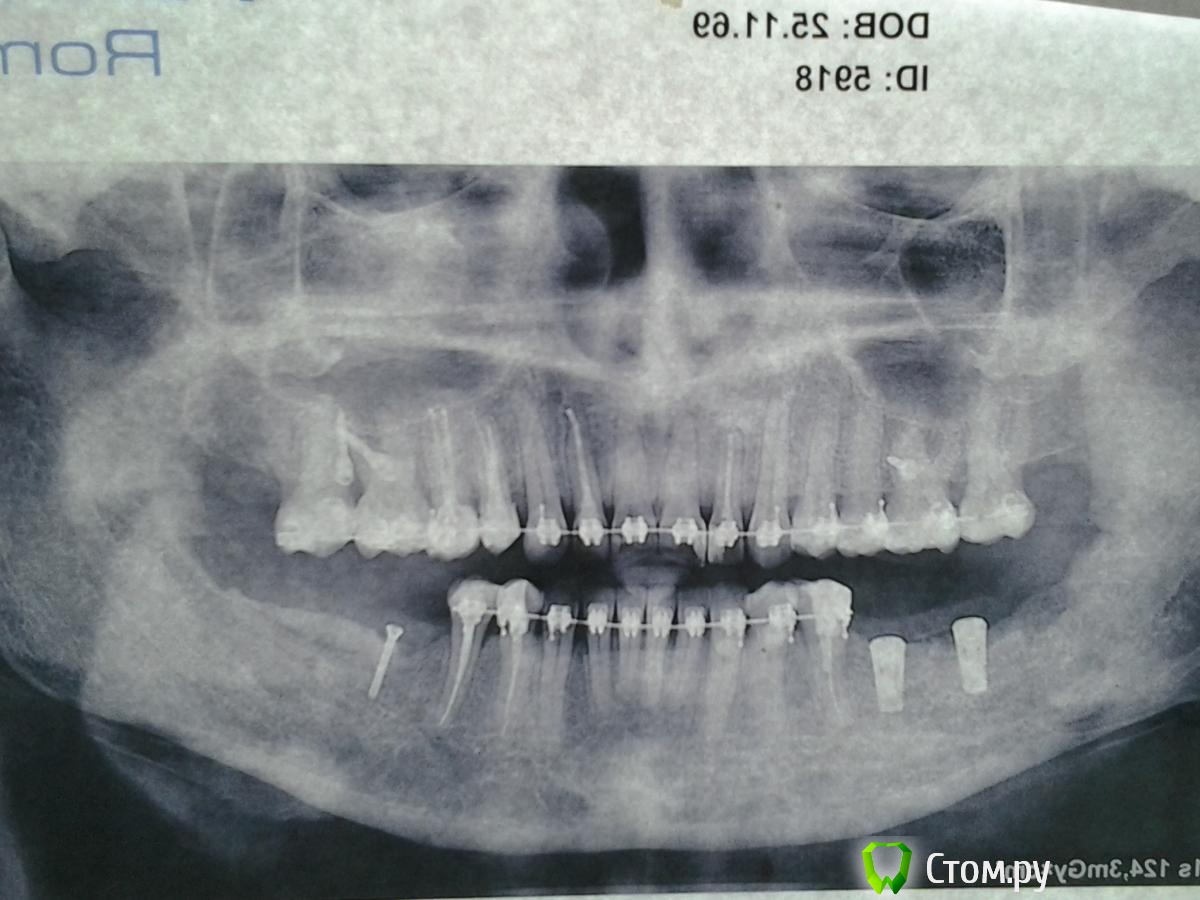

Nyurok Опубликовано 15 июня, 2014 Поделиться Опубликовано 15 июня, 2014 Здравствуйте, уважаемые врачи. С профессиональным вас праздником!Ситуация. 2 месяца назад операция "костная пластика" аутотрансплантатом. Всё хорошо, никаких субъективных ощущений. Через 1.5 месяца после операции возник сильный отек, и онемение левой половины нижней губы и левой части подбородка и практически одновременно с этим на другой стороне сделали операцию - 2 импланта и костная пластика, тоже своей костью. Принимала лекарства - кетонал, цефтриаксон, диазолин. Отек слева почти прошел, оставалась небольшая припухлость снаружи, но во рту отёк сохранялся и к тому, что было через 1 - 1.5 после операции не пришло. Справа, где импланты небольшая постоянная тупая боль. Через 2 недели от возникновения отёка (через 2 месяца после операции) в углу слева, где брали кость - открылся свищ, без заметного отделяемого, отек и онемение сохраняются. Пару дней назад справа и слева, мест забора кости, удалили некротизированные костные ткани (во время операций туда клали гемостатические губки), слева ещё удалили 1 винт из костного блока и отшлифовали верхний слой блока, зашили , место где блок. Лекарства - абактал, кетонал, диазолин.Сейчас. Справа ощущения значительно улучшились. Слева - улучшений нет. Отек, онемение, тяжесть всей левой челюсти до уха и где подчелюстные узлы.Прошу вас сказать, что есть сейчас на снимках и что делать.Состояние, как мне кажется, критическое. Надеюсь на помощь. Ссылка на комментарий

Nyurok Опубликовано 15 июня, 2014 Автор Поделиться Опубликовано 15 июня, 2014 ничего не понял, вы что снимки перевернули?Я ориентировалась где у меня право, там и снимок правой стороны. Как точно нужно - не знаю. Импланты это правая сторона, винтик левая Ссылка на комментарий

Nyurok Опубликовано 15 июня, 2014 Автор Поделиться Опубликовано 15 июня, 2014 какая зона вас смущает? обведите кружочкомизвините, не знаю как это сделать. Вся практически левая сторона нижней челюсти отличается от правой, она темнее, т.е. получается это разрежение кости? Вниз от винтика, 4-ки 5-ки до края нижней челюсти. Ведь у меня после вчерашней манипуляции нет улучшения? Значит источник инфицирования не устранен? Ссылка на комментарий

Bier Опубликовано 15 июня, 2014 Поделиться Опубликовано 15 июня, 2014 http://forum.stom.ru/topic/1640-snimok-zubov/особых проблем я не вижу на снимке. Ссылка на комментарий

Bier Опубликовано 15 июня, 2014 Поделиться Опубликовано 15 июня, 2014 на яндексфотках выбирайте ссылки для размещения на форуме (с квадратными скобками), тогда они будут в сообщениивы выложили ровно те же снимки, что и в теме.Повторюсь, буква L на снимке должна быть справа, а R слева. Ссылка на комментарий